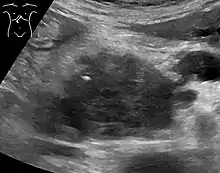

Medical imaging techniques, such as computed tomography (CT scan) and endoscopic ultrasound (EUS) are used both to confirm the diagnosis and to help decide whether the tumor can be surgically removed (its "resectability").[12] On contrast CT scan, pancreatic cancer typically shows a gradually increasing radiocontrast uptake, rather than a fast washout as seen in a normal pancreas or a delayed washout as seen in chronic pancreatitis.[56] Magnetic resonance imaging and positron emission tomography may also be used,[2] and magnetic resonance cholangiopancreatography may be useful in some cases.[32] Abdominal ultrasound is less sensitive and will miss small tumors, but can identify cancers that have spread to the liver and build-up of fluid in the peritoneal cavity (ascites).[12] It may be used for a quick and cheap first examination before other techniques.[57]

A biopsy by fine needle aspiration, often guided by endoscopic ultrasound, may be used where there is uncertainty over the diagnosis, but a histologic diagnosis is not usually required for removal of the tumor by surgery to go ahead.[12]